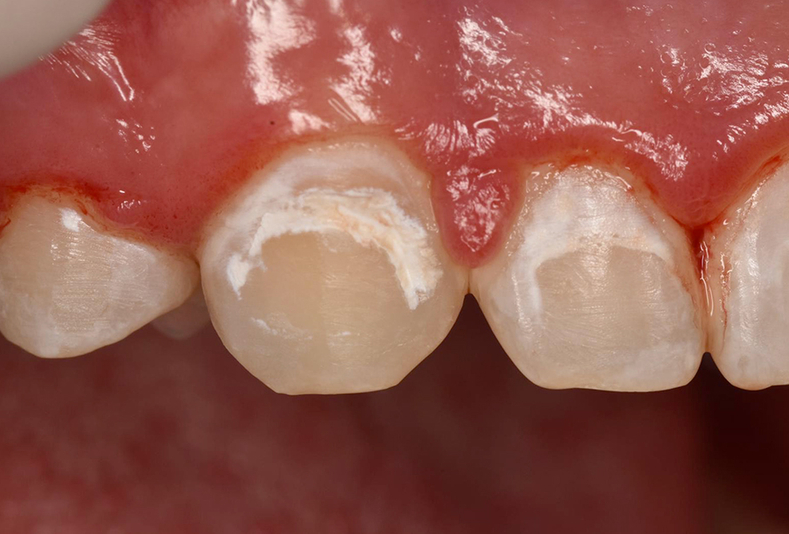

Infiltrazione resinosica per il trattamento non invasivo delle lesioni ipocalcifiche

Igiene dentale

lesioni dello smalto

Applicazione della Fluorescenza quantitativa indotta per il trattamento delle lesioni dello smalto